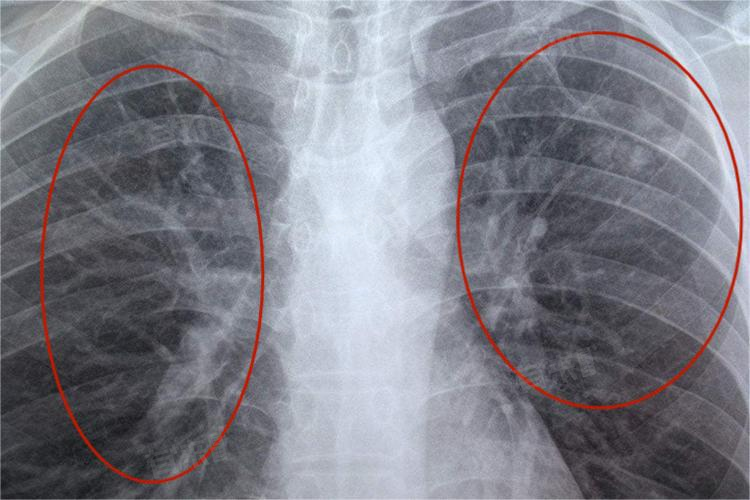

肺部索条影是否需要治疗,需根据具体情况进行综合评估。肺部索条影是在胸部X线或CT扫描中观察到的一种特征性影像表现,可能是由多种原因引起的,包括血管影、支气管壁影以及炎症或病变等。这种影像并不一定表示有病变或疾病存在,有时可能是正常的解剖结构或既往病变留下的痕迹。

- 在决定是否治疗以及选择何种治疗方法时,医生通常会综合考虑患者的症状、体征、影像学表现以及其他相关检查结果。如果索条影较小且无明显症状,可能不需要特殊治疗,只需定期复查以监测病情变化。但如果索条影较大或伴有明显症状,医生可能会建议进行进一步检查以明确病因,并制定相应的治疗方案。